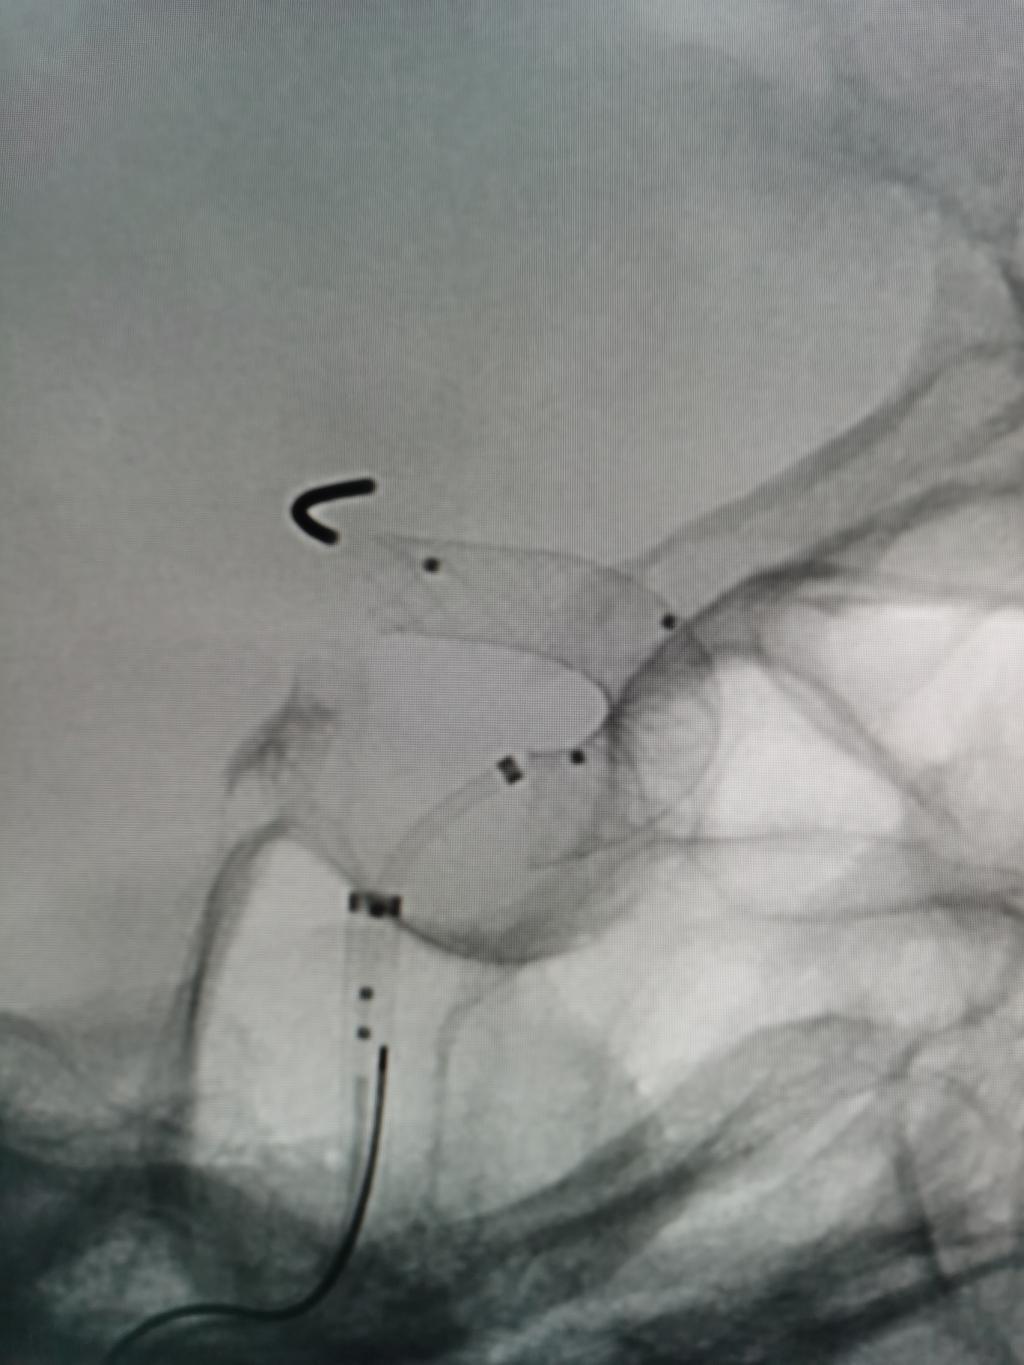

手术团队采用先进的Seldinger技术,精准穿刺患者右侧远端桡动脉并建立微创通道。术中造影清晰显示,患者左侧颈内动脉眼段存在一枚大小约4×2mm、瘤颈较宽且形态不规则的动脉瘤。

在李俊教授的精准指导与团队的密切配合下,手术医师通过纤细导管,将一枚Lattice密网支架精准输送至目标位置,成功释放在动脉瘤远近端,实现对瘤颈的完美覆盖。术后即时造影显示,动脉瘤内血流明显滞留,支架贴壁良好,载瘤动脉保持通畅,手术目标圆满达成。